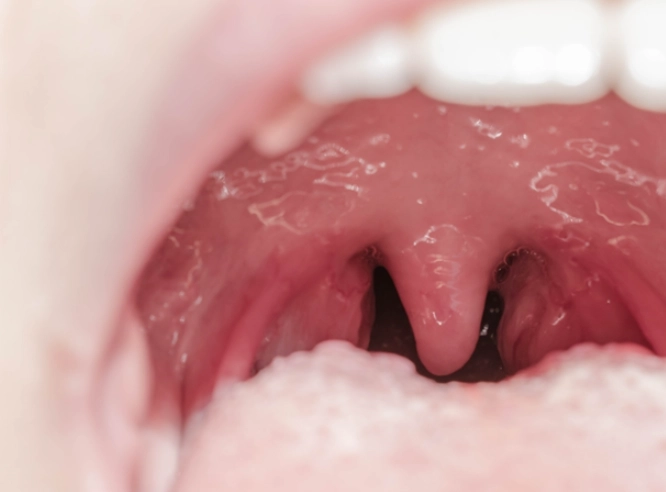

扁桃腺發炎怎麼緩解?本文提供完整的扁桃腺發炎緩解指南,從居家護理技巧到醫療治療方案,幫助你快速減輕疼痛不適,恢復健康狀態。了解有效的扁桃腺發炎緩解方法,避免併發症發生。

為什麼扁桃腺會反覆發炎?扁桃腺發炎原因究竟有哪些?本文從病毒感染、細菌感染到免疫力下降等角度,完整解析扁桃腺發炎的成因,並提供實用預防建議,幫助您遠離喉嚨不適。